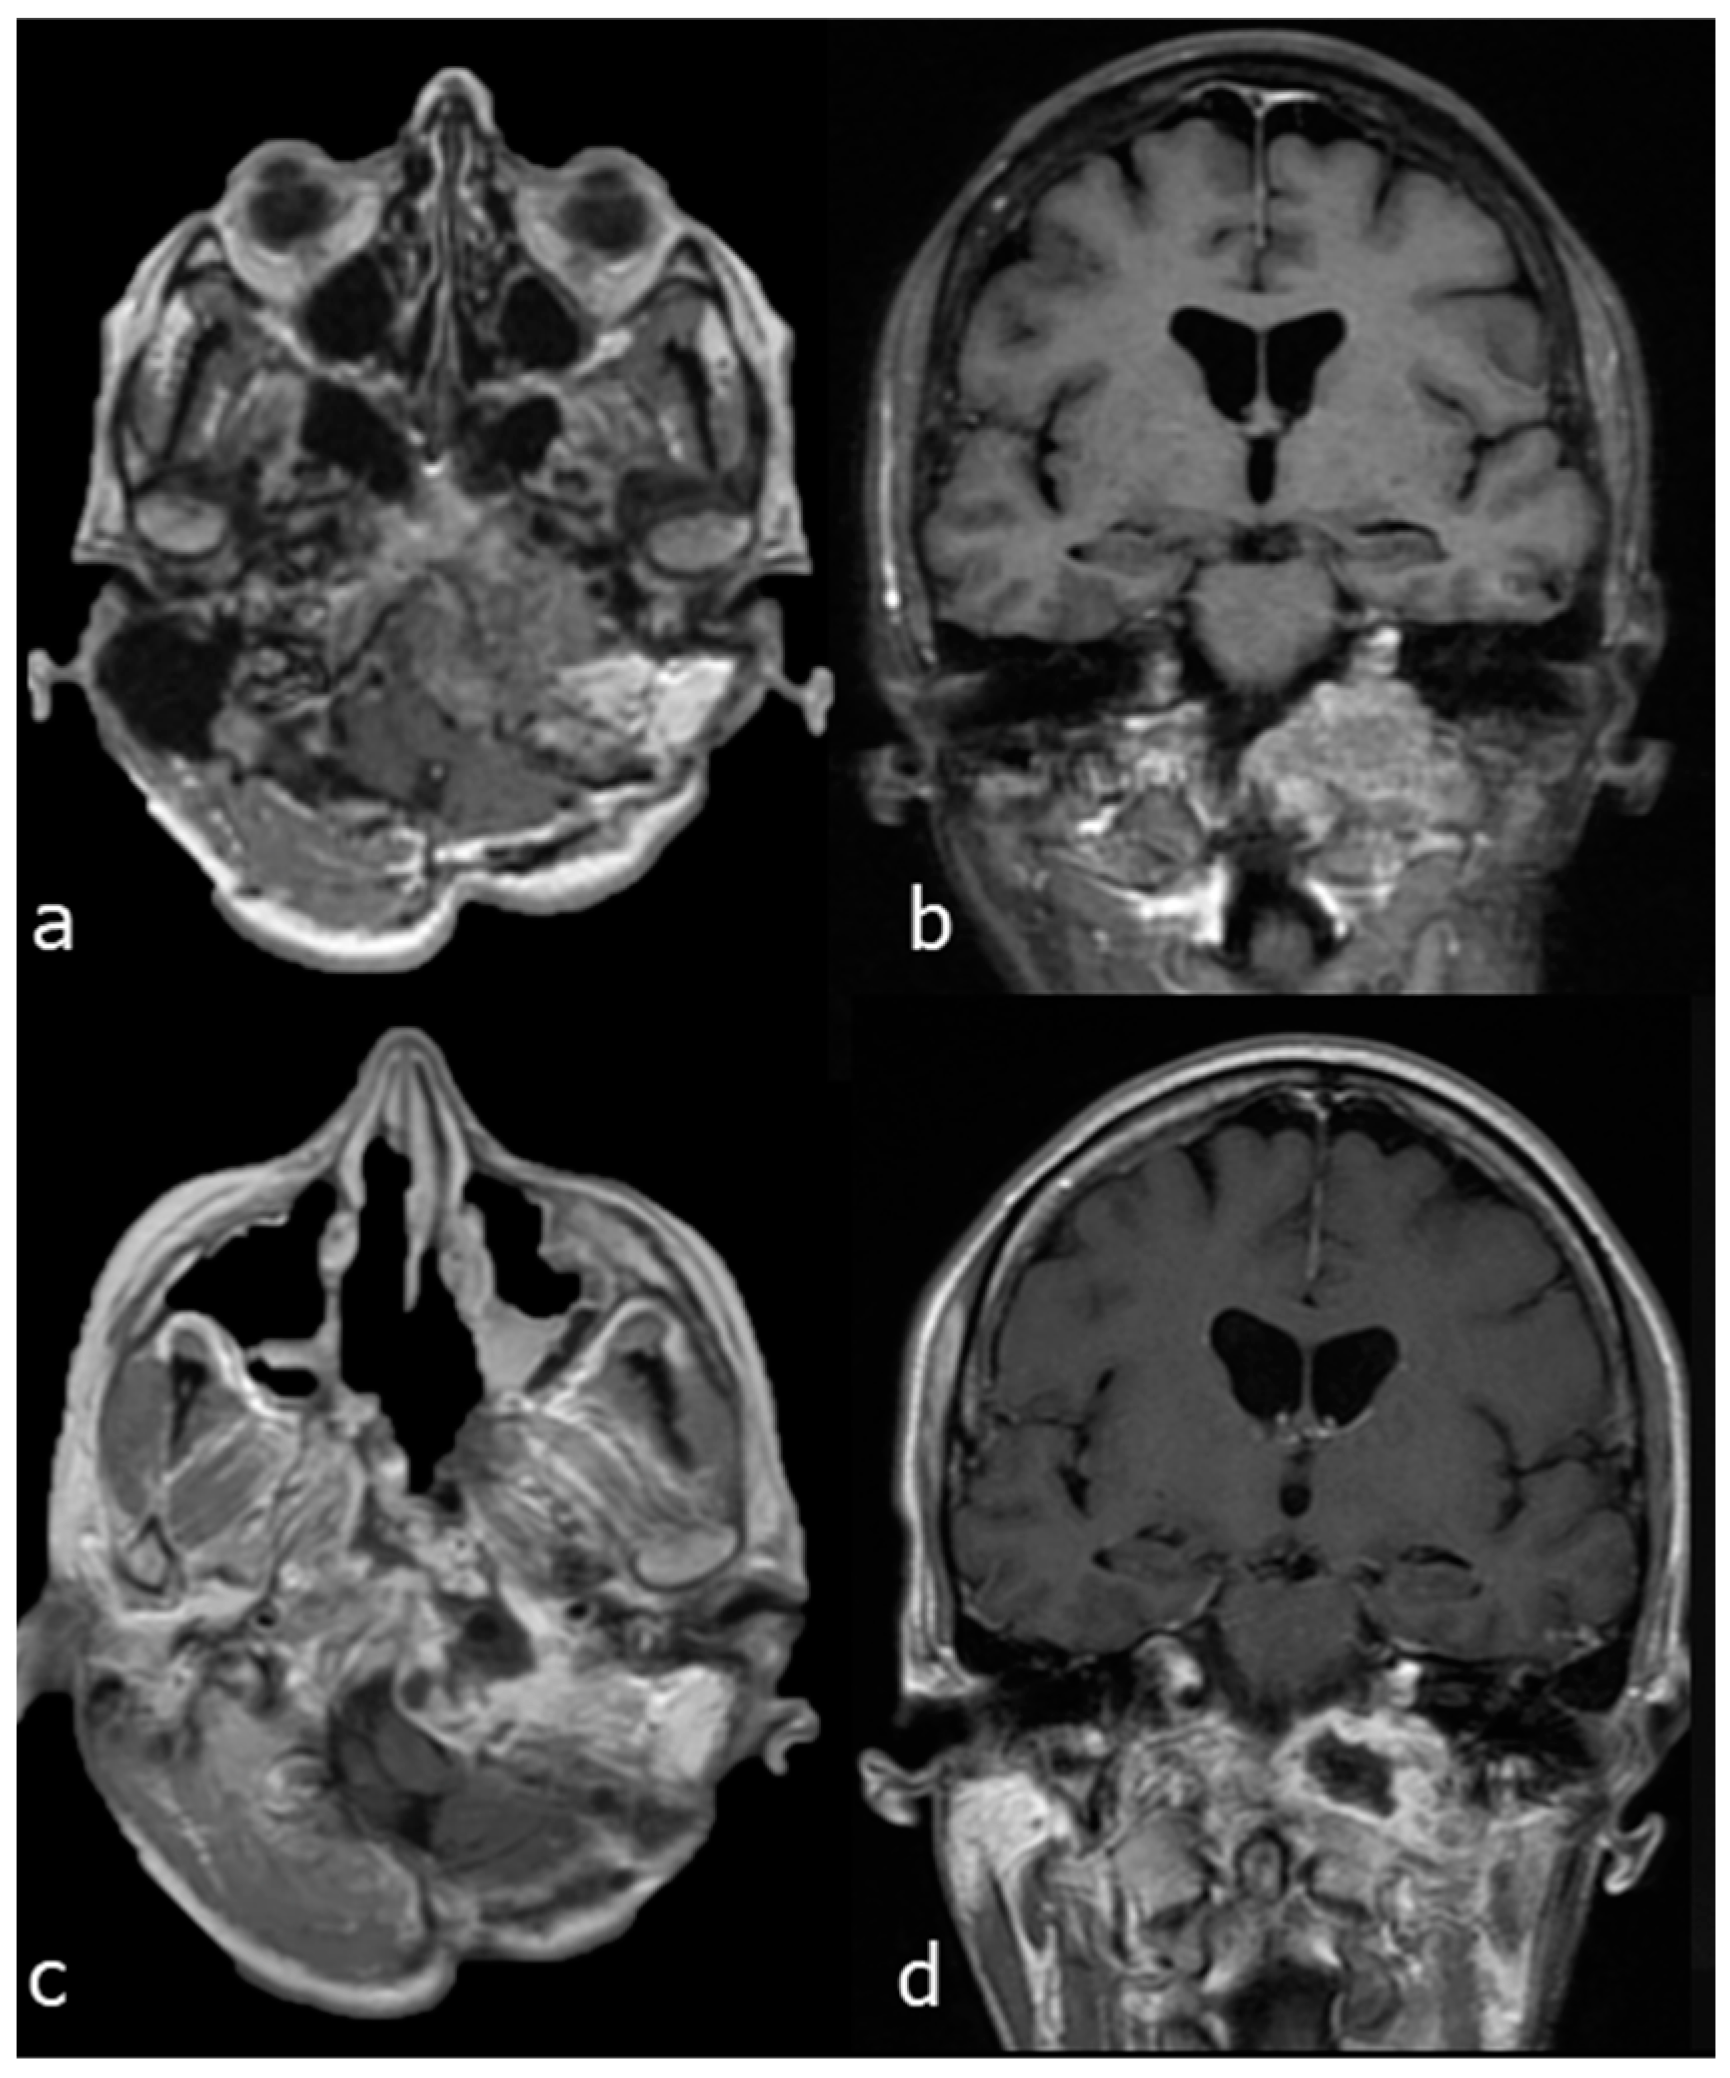

A 44-year-old woman affected by a large cranio-cervical junction chordoma subtotally resected through a retrosigmoid craniotomy 5 years before presented a slowly progressive tumour recurrence. A contrast-enhanced brain MRI showed a significant bilateral invasion of the petroclival region, with remarkable brainstem compression and displacement, and an extension towards the left parapharyngeal space. The patient presented with dysphonia and mild dysphagia. The tumour was approached through a combined EETC, left trans-pterygoid and CTM approach. The pcICA was exposed on the left side. Tumour resection was started through the endonasal corridor to remove the brainstem extradural component of the lesion. Then, the left parapharyngeal tumour portion was accessed using the endonasal corridor for endoscopic visualization and the transmaxillary route for surgical resection. A right nasoseptal flap was used for skull base reconstruction. Near total resection was obtained, as shown by the postoperative MRI (Figure 6).

Figure 6.

Case 1: preoperative and postoperative MRI scans of a large cranio-cervical junction chordoma, underwent first surgery through a retrosigmoid craniotomy, and then operated on by a combined EETC and CTM approach. (a) preoperative MRI scan, axial view. (b) preoperative MRI scan, coronal view. (c) postoperative MRI scan, axial view. (d) postoperative MRI scan, coronal view.